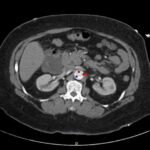

Acute aortic dissection is a life-threatening event caused by separation of the aortic layers that requires prompt management and surgical consultation. We present the case of a 53-year-old male who developed acute, severe chest pain radiating to his back at a community hospital and was transferred to a tertiary center for definitive surgical management. The patient’s aortic dissection was diagnosed via computed tomography angiography. He was started on rate-control and blood pressure medications, and was admitted emergently to the operating room. Emergency physicians should obtain immediate surgical consultation, promptly start medications for rate and blood pressure control, and administer analgesia in order to stabilize their patient and decrease the shear forces that would further propagate an aortic dissection.